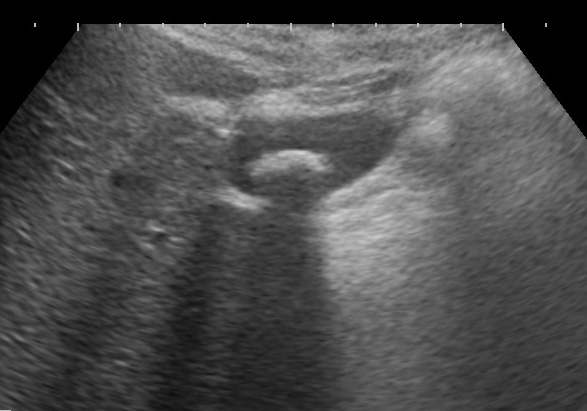

慢性膵炎は繰り返す上腹部痛や背中の痛みなどを主な症状とし、正常な膵臓の組織が消失して線維性の硬い組織に置き換わった状態です。超音波検査などで膵管内に石を認めたり、膵臓のやせ(萎縮)を認めたりします。慢性膵炎の原因はアルコールとそれ以外に大別されます。アルコール以外の原因には家族性・遺伝的なものや自己免疫性(体の中に自分の組織を攻撃する抗体ができてしまう)などがあります。進行すると膵臓の消化液や血糖をコントロールするインスリンの分泌が悪くなったりします。治療には飲み薬による消化酵素の補充や糖尿病のコントロールなどがあります。

気を付けなければならないのは膵癌によって膵炎がおこり、糖尿病の発症や、糖尿が悪化するなどの場合があることです。このように糖尿が急に起こったり急に悪化したりする場合には膵癌の存在を考えて超音波検査などの画像検査を行う必要があります。

腹部超音波検査(腹部エコー)について

腹部エコーは超音波振動の出るプローブと呼ばれる機械を体の表面にあてて超音波の跳ね返りで体の内部を検査する装置です。当クリニックでは富士フイルムヘルスケア社の超音波診断装置を使用しています。当クリニックの腹部エコーでは臓器の形だけでなく、血管内の血流評価や肝臓の硬度測定・脂肪化推定なども可能です。超音波用のゼリーをつけて機械を当てるだけの検査ですので痛みはありません。胃内に食事があると観察不良となりますので午前中なら朝食、昼からなら昼食を抜いた上で検査を行っています。